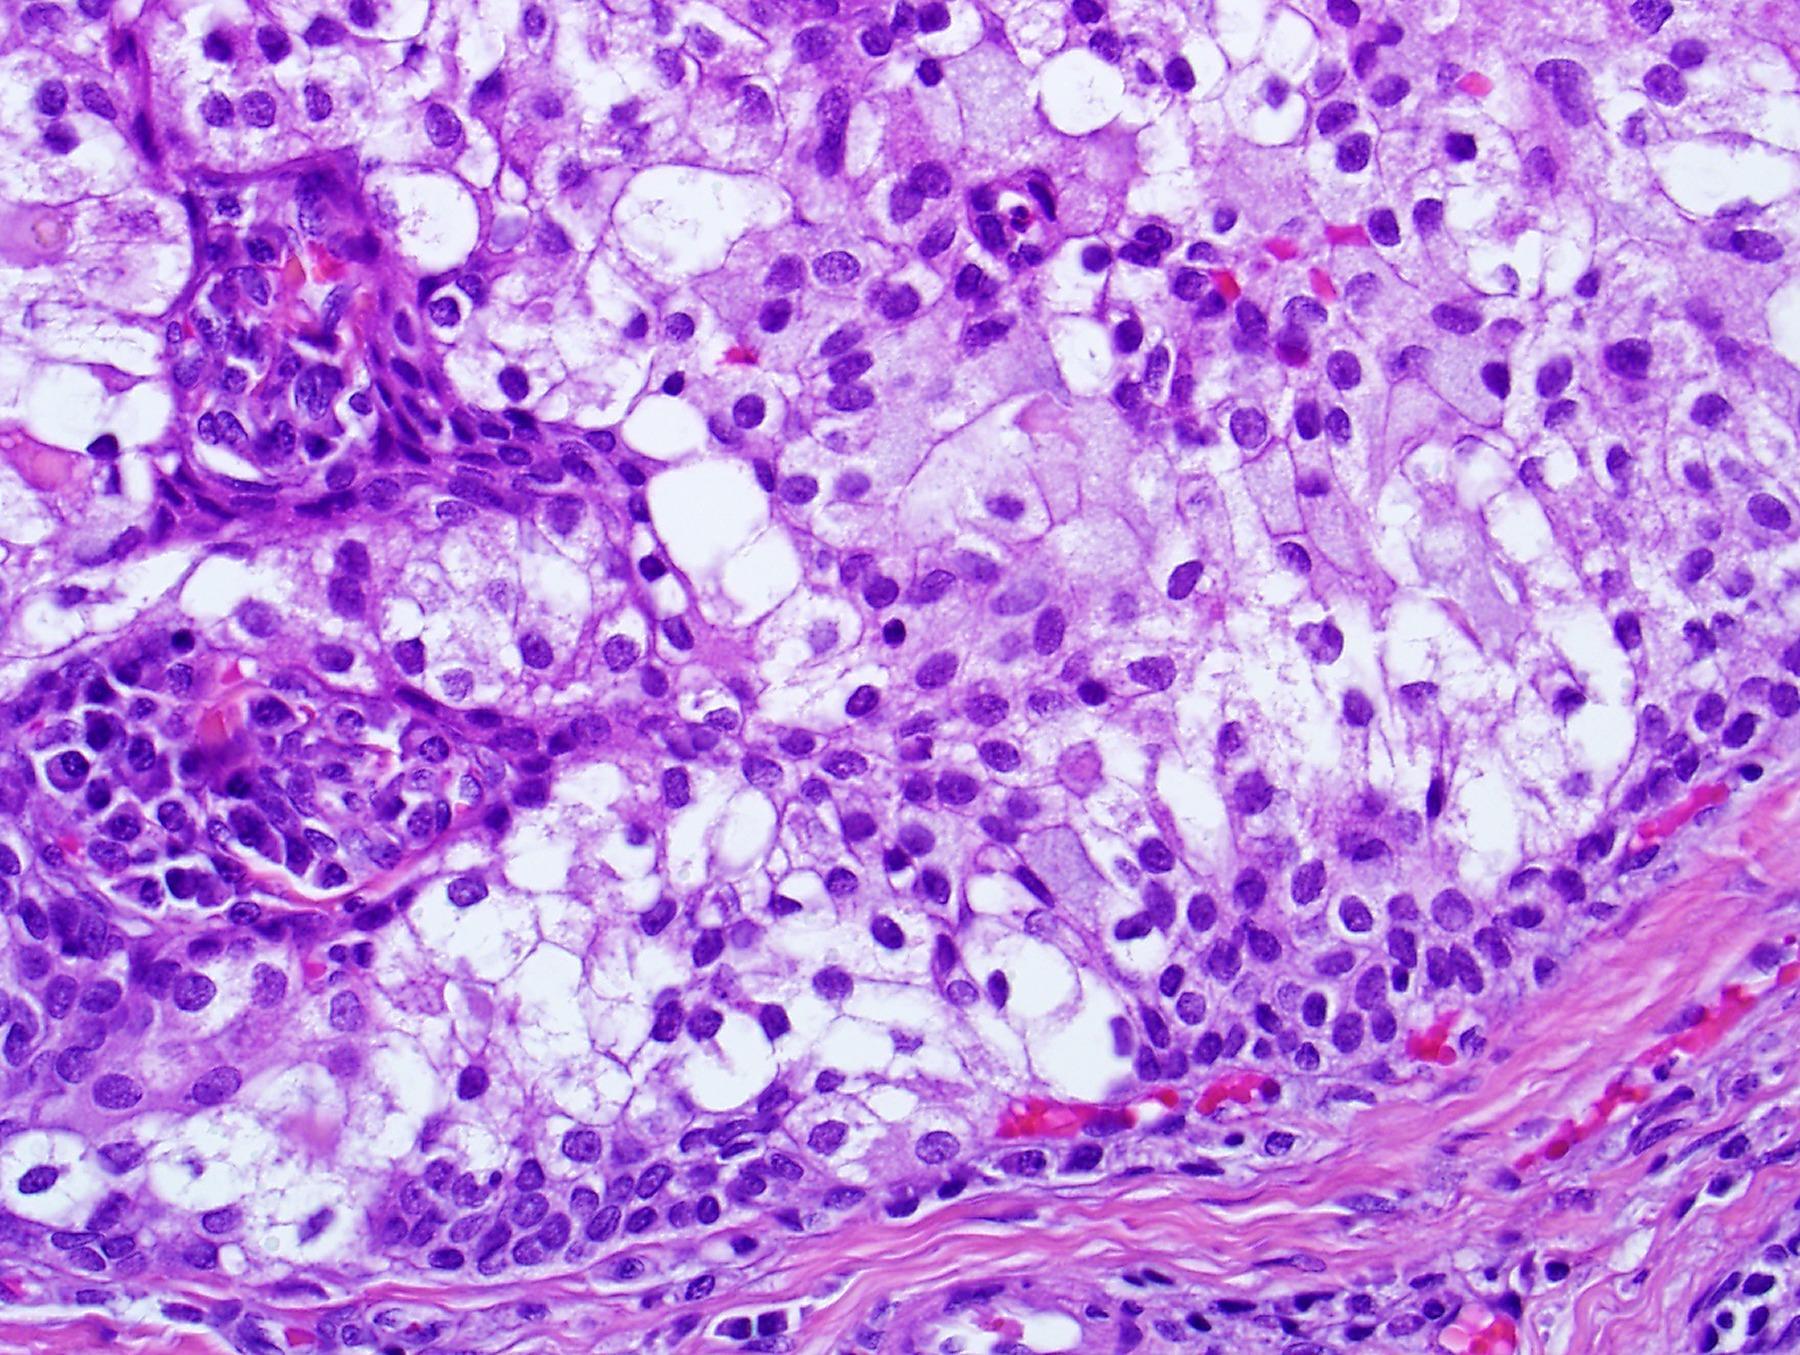

Case 12 55-year-old, Male Lump In Parotid.

??

Case 12 Diagnosis

Acinic cell carcinoma

Notes • Lymphoid

• ACC • MEC • Prognostic factor- better

indicator • ACC can undergo HG transformation

stroma

prognostic